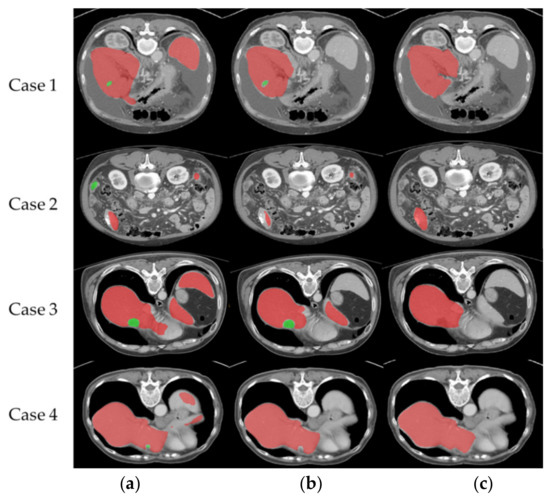

4.4. Misidentification of Liver Volume and Pathological Data Comparison